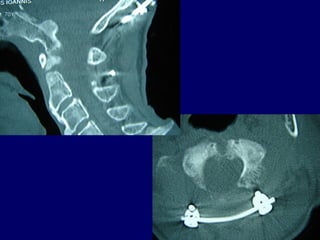

CervicalCervical

epiduralepidural

abscessabscess

Anterior decompressionAnterior decompression

±± stabilizationstabilization

Posterior decompressionPosterior decompression

PosteriorPosterior

decompressiondecompression

andand

stabilizationstabilization

22ndnd

casecase

J. Chr.

M 69

Unknown origin

Symptoms

Neurologic deficit

Pain

Low fever

MRIMRI

TransoralTransoral

Pus evacuationPus evacuation

Follow upFollow up

Antibiotics

i-v for 2 weeks

orally for 4 months

(staphylococous aureous)

Complete neurologic recovery